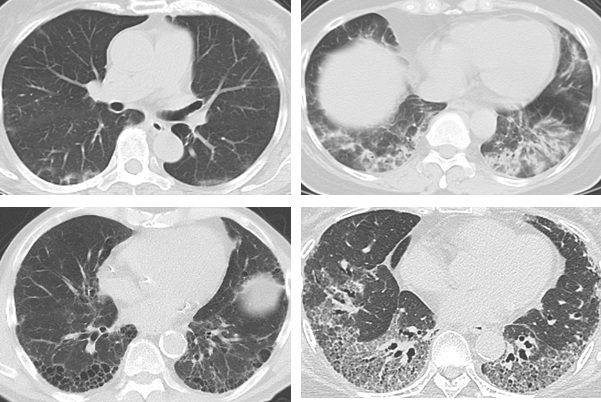

ILDのCT画像(個々の症例に応じてILDの画像特徴が異なる)

ILDの進行の速さ、治療反応性、予後は、個々の症例によってきわめて多様性があり、 抗MDA5抗体や抗ARS抗体などの自己抗体の情報のみで治療方針を決めることは困難である。肺病変の進行速度・範囲・分布、血液中酸素化や肺活量などの肺機能など包括的に評価して、治療方針を決定する必要がある。